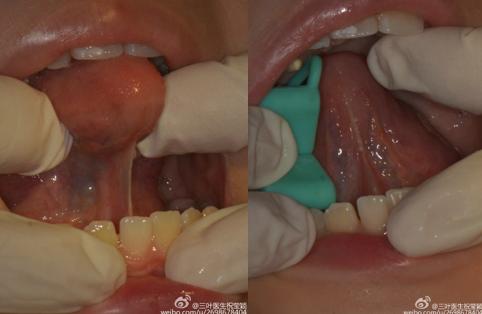

舌系带俗称“舌筋”,

是口底和舌尖相连的一条粘膜皱襞。

目前有多种舌系带延长的手术方式,比较先进的是激光无痛手术:安全,无痛,迅速(手术只需几分钟),几乎不用缝合,愈合速度较快,创面恢复较好。